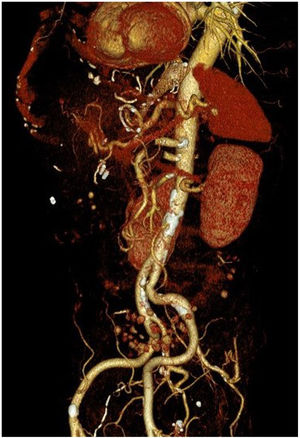

However, 24 h later, he was readmitted for haematemesis with normal CT angiography (Fig. 1), and endoscopy was performed to control the haemorrhage by means of clips without adequately visualising the endoprosthesis. After a new endoscopy at 8 h, the endoprosthesis was removed and haemostasis was checked, apparently adequate. Five days later, the patient presented with a new haemorrhage with instability, and endoscopic control was not achieved, so urgent open surgery was decided on suspicion of aorto-oesophageal fistula. The review of the CT angiography, prior to removal of the endoprosthesis, supports the diagnosis by showing the proximity of the proximal portion of the endoprosthesis to the aorta, as shown in the 3D reconstruction (Fig. 2). During surgery, the fistula was confirmed and repaired with direct aortic suture. For visualisation, the oesophago-jejunal anastomosis had to be undone and oesophagectomy, cervical oesophagostomy and feeding jejunostomy were performed.